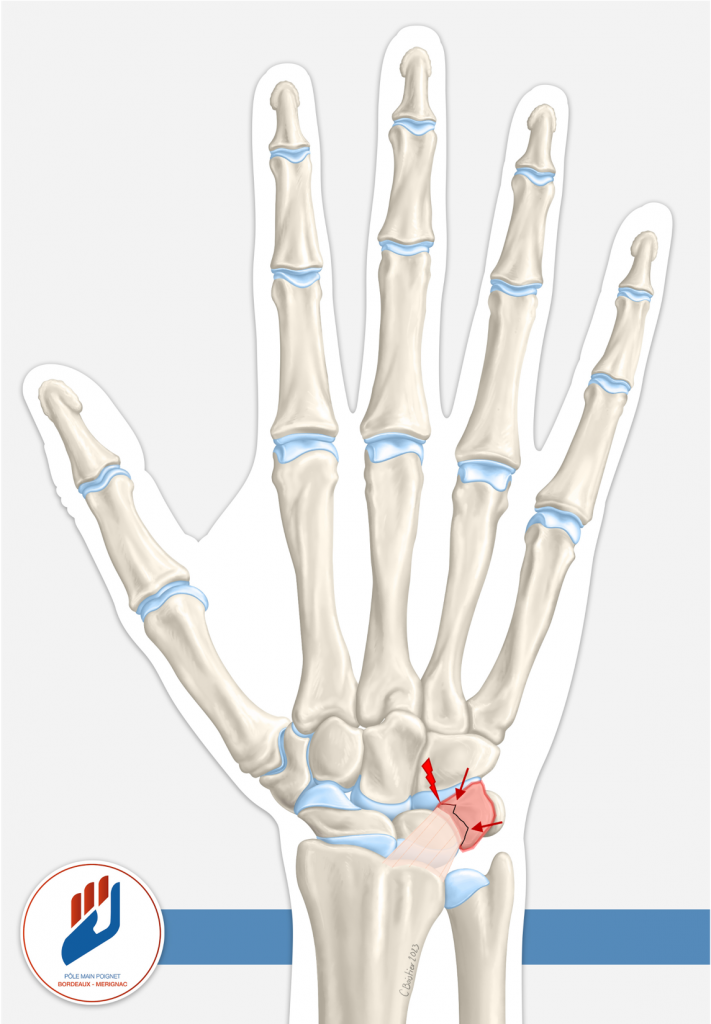

Souvent, la fracture du triquétrum se présente sous forme d’une « fracture-chip » (un petit fragment osseux détaché) sur la face dorsale de l’os au point d’insertion du ligament radiocarpien dorsal (cf schéma). D’autres formes plus complexes (fracture du « corps » du triquétrum ou fracture sur la face palmaire) peuvent aussi exister, notamment dans des traumatismes plus sévères.

- Indiqué lorsque la fracture est complexe, déplacée ou associée à une instabilité du poignet.

- Il peut s’agir d’une réduction et fixation avec des vis ou broches.